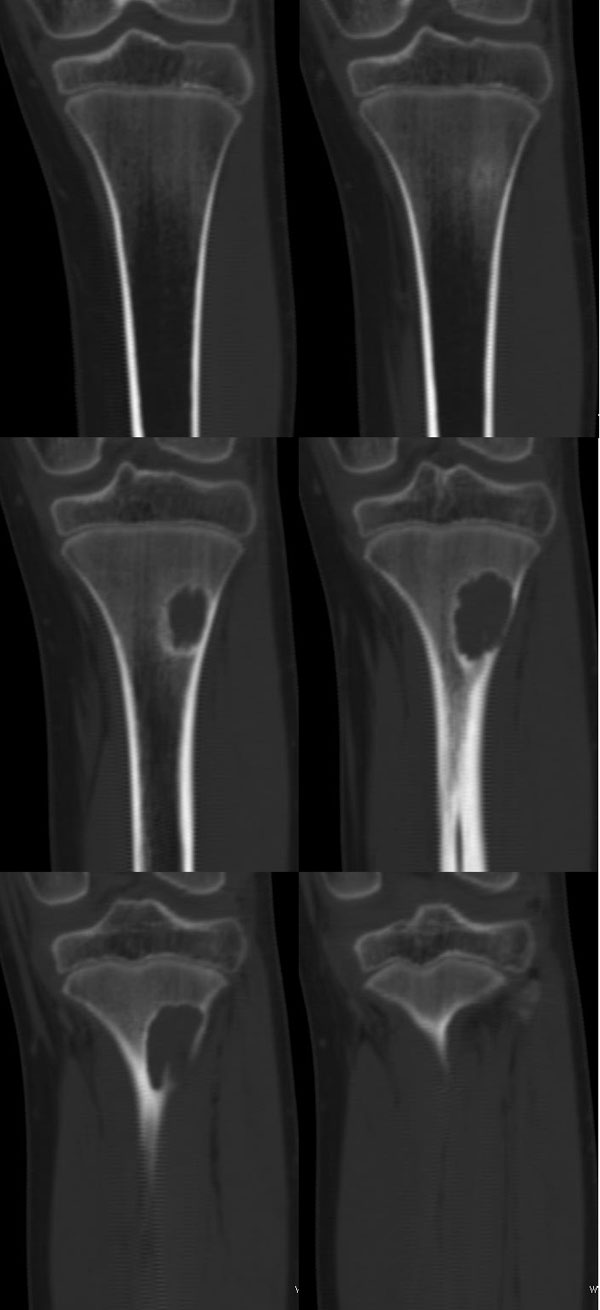

以下是引用37度在2010-1-7 12:22:00的发言:[br]左胫骨上段纤维性骨皮质缺损(非骨化性纤维瘤).

以下是引用dyqct在2010-1-7 14:54:00的发言:[br]考虑为左胫骨上段纤维性骨皮质缺损 ,可自愈.

以下是引用沉默是金在2010-1-8 18:51:00的发言:[br]非骨化性纤维瘤

以下是引用xkncyyhyq在2010-1-7 9:54:00的发言:[br]考虑为纤维性骨皮质缺损